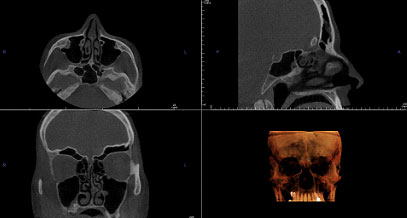

Jest nią trójwymiarowe badanie tomografem komputerowym (metoda obrazowa oceniającą morfologię tkanek).

Jest to badanie nieinwazyjne, bezbolesne, krótkie (trwa ok. 10-15 sekund). Obecnie, nowoczesne aparaty tomograficzne używają bardzo niskich dawek promieniowania, a co za tym idzie, są bardzo bezpieczne. Dzięki tomografii komputerowej możemy ocenić obecność zmian zapalnych w zatokach, drożność ujścia zatok do nosa, anatomię nosa i zatok.